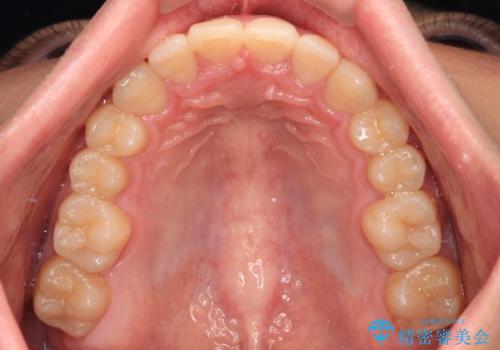

傾斜しいている大臼歯を立ち上げながら、下顎歯列を上顎に対して前方位となるように工夫し、デコボコを解消した上でディープバイトも改善することができました。